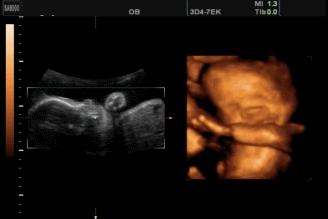

导读:怀孕五个半月,胎儿会笑吗?为什么?

苗苗怀孕5个半月的时候去做四维彩超,她一直注视着大屏幕上宝宝的一举一动。忽然,她看到胎宝宝咧嘴笑了,这给她大大的惊喜,同时,她又很惊讶,宝宝在肚子里也会笑?常听说宝宝出生后还不会笑呢?

其实,关于胎宝宝在肚子里微笑,类似的报道并不少见,很多妈妈反馈过做四维时看到宝宝笑的样子,国外媒体也经常报道类似的新闻。

2003年,英国《卫报》报道,科学家用4D超声波成像系统拍到了26周宝宝微笑的图片。

2018年,英国《每日邮报》报道,一对夫妇在做四维彩超时发现宝宝咧嘴微笑,让父母感到喜出望外。

见诸各大网站的3D胎儿图像,也展示了胎儿在19周时微笑的模样,栩栩如生,惹人喜爱。

怀孕5个半月,胎儿已经有了面部表情,喜怒哀乐都会有,当然胎儿也会发笑。

从这里看出,在做四维彩超的时候很容易捕捉到胎儿的微笑,这时不要觉得奇怪,这是胎儿正常的生理反应。